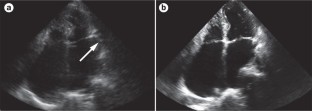

Transoesophageal echocardiography is the gold standard for the evaluation of LAA stasis and thrombosis, and promising results have been reported for intracardiac echocardiography and transthoracic echocardiography with contrast

Manning, W. J., Silverman, D. I., Gordon, S. P., Krumholz, H. M. & Douglas, P. S. Cardioversion from atrial fibrillation without prolonged anticoagulation with use of transesophageal echocardiography to exclude the presence of atrial thrombi. N. Engl. J. Med. 328, 750–755 (1993).

Aschenberg, W. et al. Transesophageal two-dimensional echocardiography for the detection of left atrial appendage thrombus. J. Am. Coll. Cardiol. 7, 163–166 (1986).

Hwang, J. J. et al. Diagnostic accuracy of transesophageal echocardiography for detecting left atrial thrombi in patients with rheumatic heart disease having undergone mitral valve operations. Am. J. Cardiol. 72, 677–681 (1993).

Manning, W. J. et al. Accuracy of transesophageal echocardiography for identifying left atrial thrombi. A prospective, intraoperative study. Ann. Intern. Med. 123, 817–822 (1995).